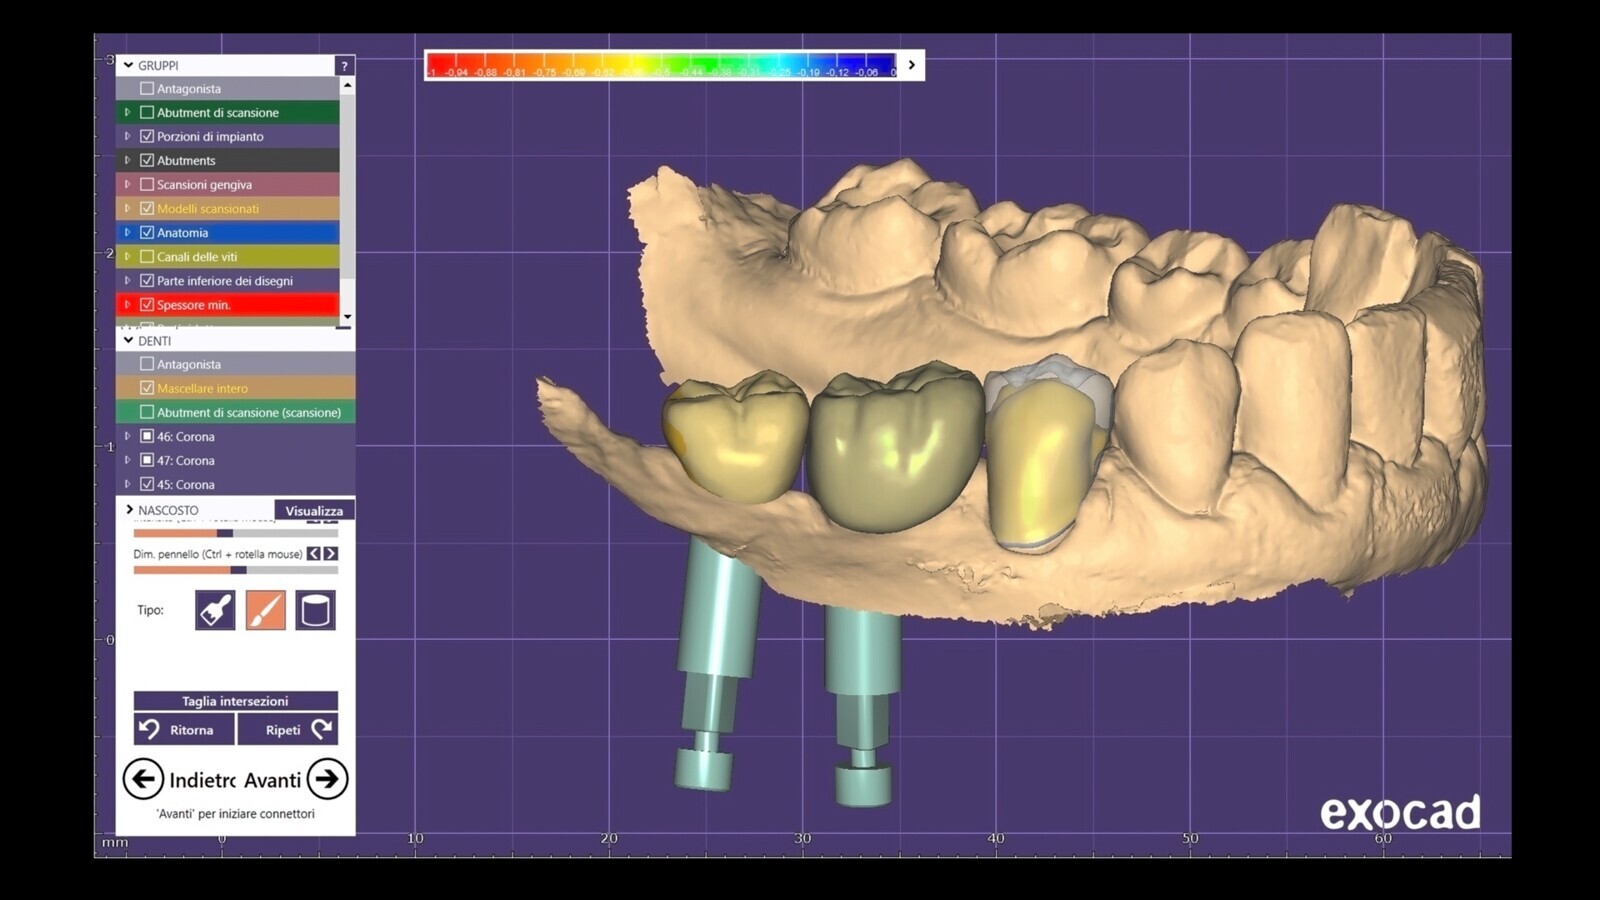

Figura 26. Posteriormente se rediseñó en el laboratorio (a) después de realizar las modificaciones apropiadas (b).

Figura 27. Una vez salvadas las morfologías, se diseñaron las coronas finales.

Figura 37. El control radiográfico muestra una buena correspondencia entre los elementos naturales, los implantes y los componentes protésicos.